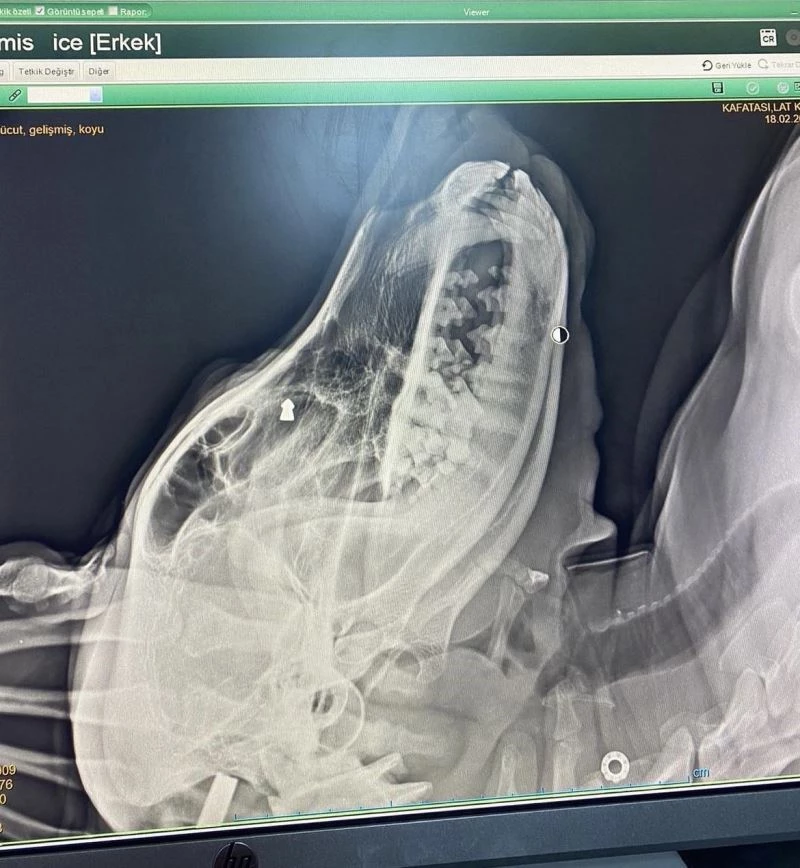

Zonguldak’ın Çaycuma ilçesinde geçtiğimiz aylarda sokak köpeğini silahla vuran şahıs, yakalanarak gözaltına alındı. Köpek tedavi altına alınıp sağlığına kavuşurken, şüpheli ise adli kontrol şartıyla serbest bırakıldı.

Olay, ilçenin İstasyon Mahallesi’nde meydana geldi. İddiaya göre, geçtiğimiz aylarda mahallede dolaşan sokak köpeğine, aracında oturan F.K. adlı kişi silahla ateş etti. Ciğerleri parçalanan köpek yol kenarına düştü. Çevredeki duyarlı vatandaşların ihbarı üzerine bölgeye polis ekipleri sevk edildi. Suçunu kabul eden F.K. gözaltına alınırken, yaralı köpek ekipler tarafından veteriner kliniğine götürülerek tedavi altına alındı.